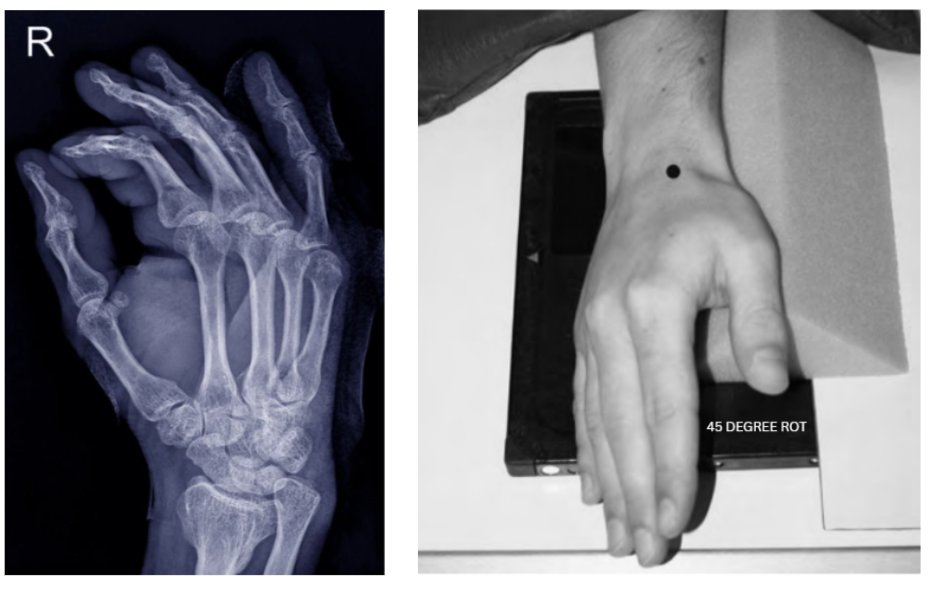

2. PA Oblique Hand X-ray

- Purpose: Assess metacarpal fractures and joint spaces with reduced superimposition of structures.

- Positioning Steps:

- Rotate the hand externally (laterally) 45° from the PA position.

- Use a radiolucent wedge to maintain the oblique angle if necessary.

- Direct the CR perpendicular to the third MCP joint.

- Pro Tip: Check for equal spacing between the metacarpal heads and avoid overlapping of digits.